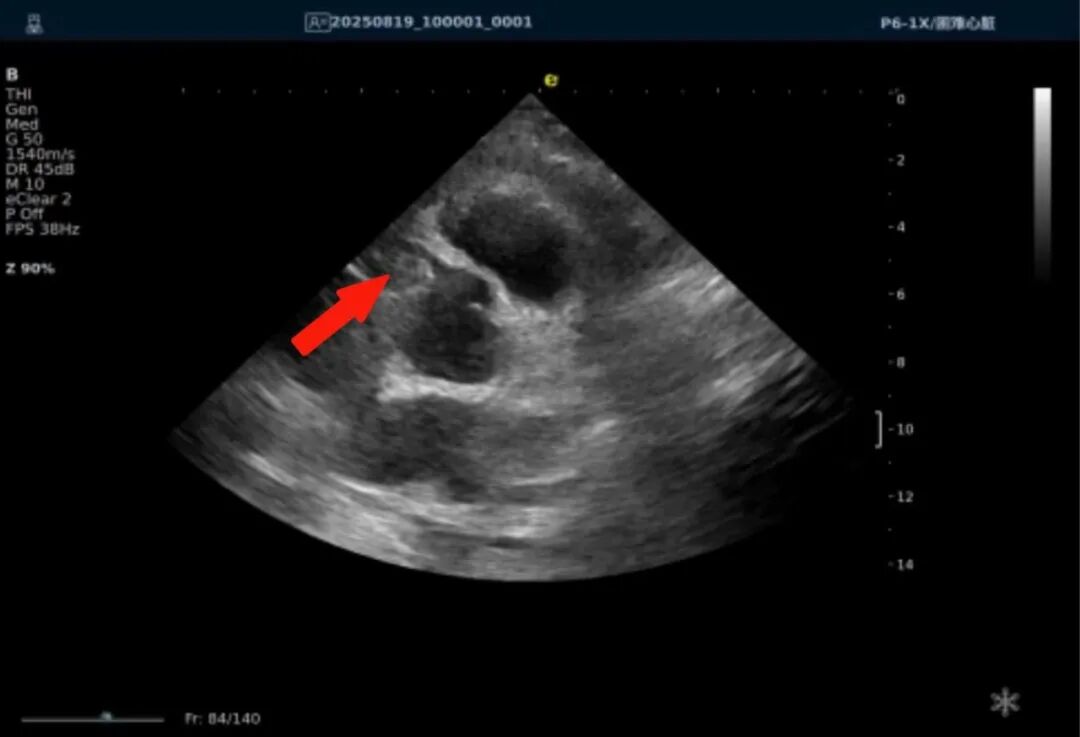

以下为逸超医疗(ESI)设备采集的冠脉图像,清晰展示了其在二维成像、彩色多普勒及频谱多普勒方面的表现:

病例实例

一、冠脉超声与CTA的协同诊断价值体现

一例胸闷患者,临床采用无创冠脉超声作为初步评估手段,检查中发现:

彩色多普勒:敏感捕捉到局部血流加速现象;频谱多普勒:测得峰值血流速度明显升高,频谱形态异常。

基于超声提示的异常发现,临床为患者安排了冠脉CTA检查,结果显示前降支近段存在约45%狭窄,与超声提示的血流动力学改变高度一致。

这一病例体现了冠脉超声作为初筛工具的重要价值:它能够无创、实时地评估冠脉血流动力学状态,为后续是否需要进一步影像检查提供重要参考。超声与CTA的协同应用,既能评估结构变化,又能反映功能状态,为临床诊断提供了更全面的信息。